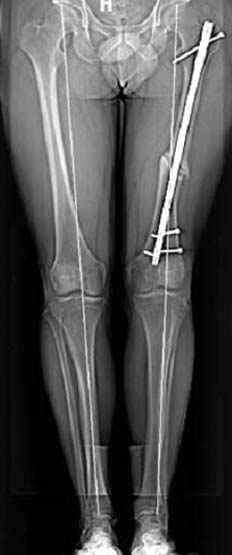

пластическая модель; и коррекция бедра аппаратом Илизарова.

хотя даже если бы и инфекция , то nail exchange с рассверливанием канала - вариант дебрайдмента) Я думаю, что последовательность развития событий:

Узкий к-м канал - тонкий гвоздь- усталостный перелом дистальных винтов - развитие нестабильности и как ее результат остеолиз вокруг гвоздя - деформация анатомической оси бедра. Похоже, что я понял почему аппарат, а не новый гвоздь:-)

ЕТ - Изначально костно-мозговой канал бедра был узкий, дальнейшее его рассверливание ещё больше скомпрометирует прочность бедра( латеральный кортекс дистального отломка уже истончен), приведет к дефекту наружной стенки - хотя это только мои догадки - хотелось бы знать мнение Джолдаса о выбранной тактике.